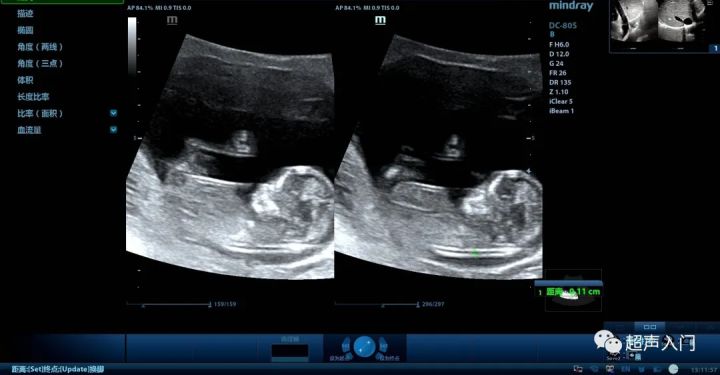

颈项透明区(NT) :胎儿颈后部皮下组织内液体积聚的厚度,为颈部皮下无回声层。

正常NT的厚度随孕龄增长而增厚,至孕13周达最大,中孕期自发消退。最佳测量时间为孕11-13+6周。NT厚度测量的正常值<3mm。